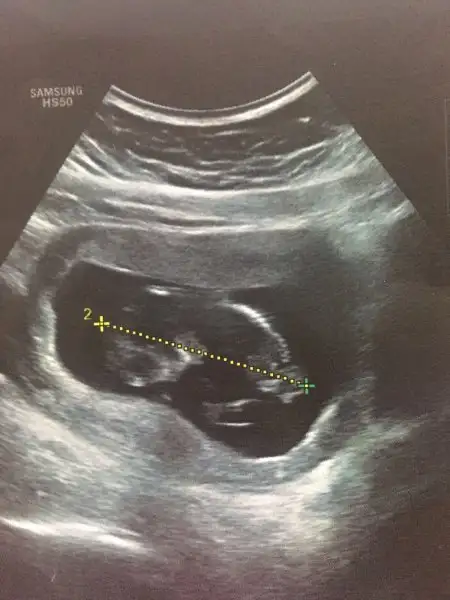

Kızlar ben döndümmm :) Türkiye'de 15 gün kaldım ve koşuşturmadan hiiiç KK'ya bakamadım. Ne kadar çok yazışma yapmışsınız :) 2 'li testimi yaptırdım. Şükür bir risk çıkmadı. Muhakkak aranızda cinsiyet öğrenen olmuştur. Gelelim benim daha önce denediğim ve tutan bir tahmine.. İkili testte yer alan T-Hcg test sonucu eğer 50'nin altındaysa kız 50'den fazla ise erkek deniyor. Doktor bu gittiğimde cinsiyet tahmini yapamadı. Ama ikili testte T-hcg değerim 80 çıktı. İkili test yaptırıp, doktordan bebeğin cinsiyetini öğrenenler bu değerlerini bir kontrol edebilir mi? bakalım doğru çıkacak mı?